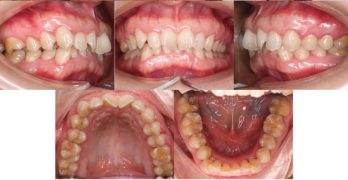

Tratamiento ortopédico de una maloclusión de clase III con mordida cruzada anterior profunda y discrepancia transversal

El artículo que compartimos el día de hoy con uds se llama Orthopedic Management of a Class III Malocclusion With Deep … [Leer más...] acerca de Tratamiento ortopédico de una maloclusión de clase III con mordida cruzada anterior profunda y discrepancia transversal